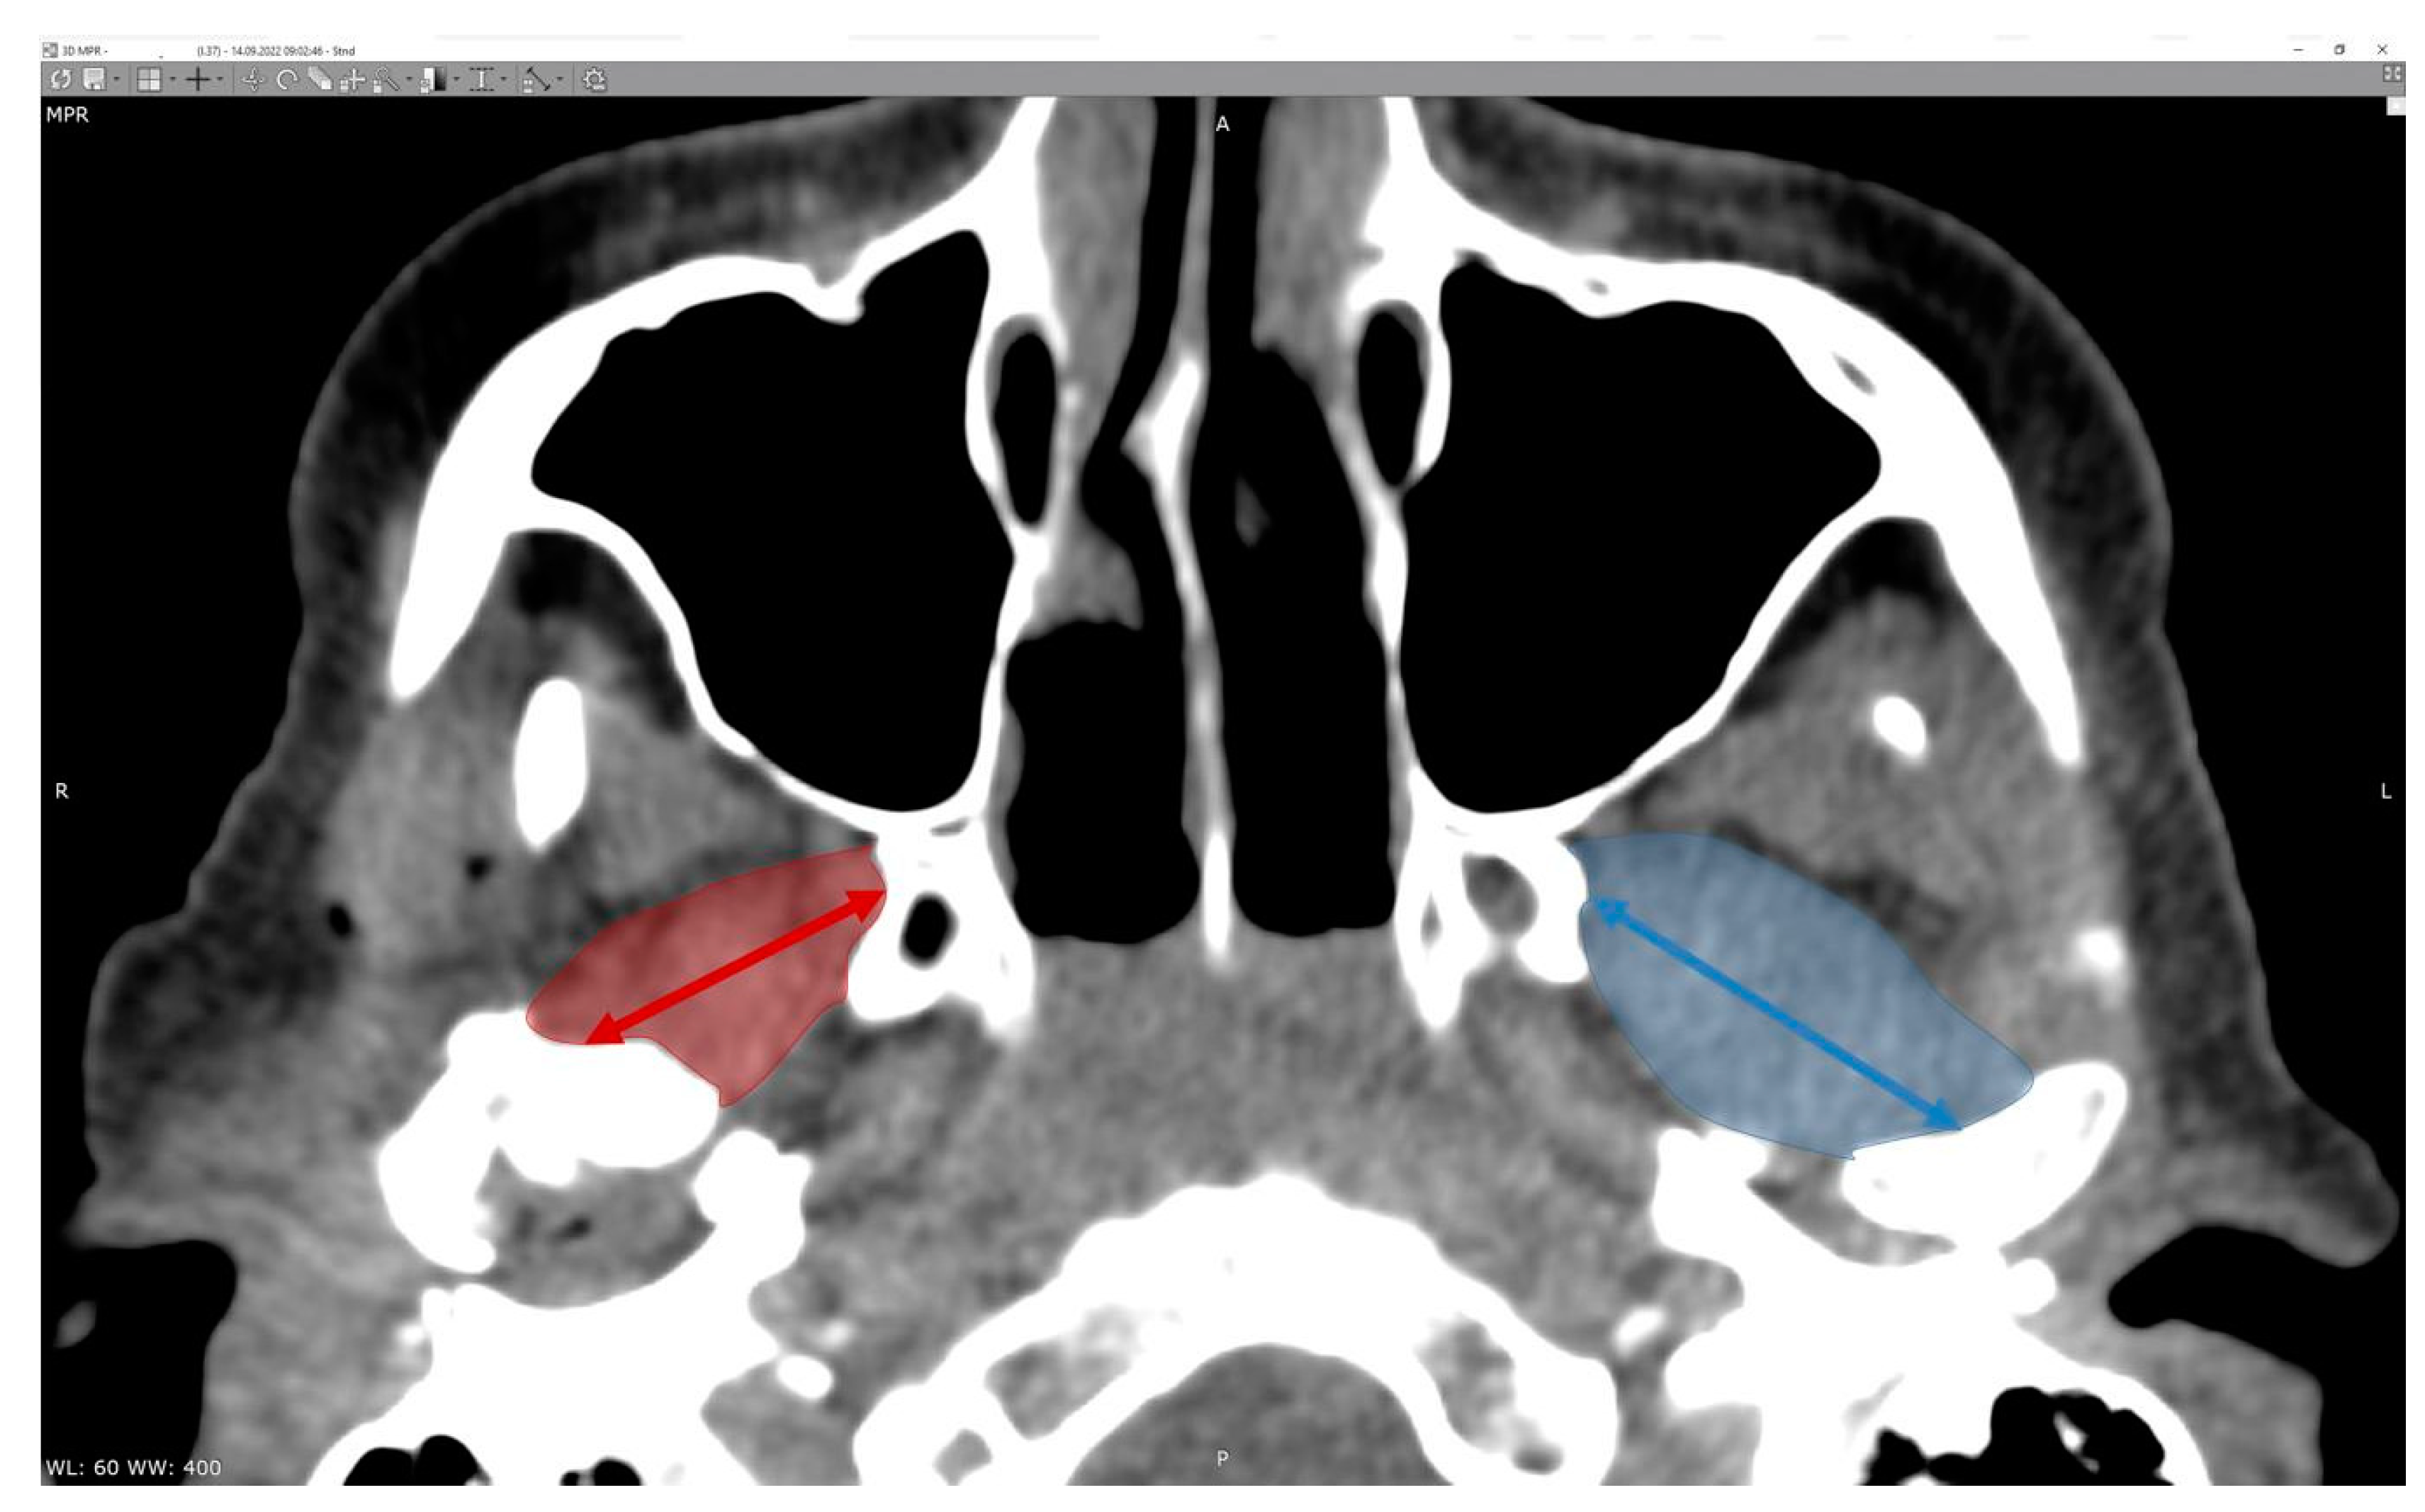

There is no doubt that surgical correction is the only way to restore the anatomical position of the mandibular head; however, the question is if it also improves the condition of the lateral pterygoid muscle, which, at first glance, right after the injury, shows significant asymmetry in terms of its shape (Figure 2).

The study began with measurements of the greatest length and width of the lateral pterygoid muscle. The results are presented below (Table 2 and Table 3). The muscle measurements at the immediate post-operative timepost are expected to be affected by soft tissue trauma; therefore, the measurements were repeated in four other timepoints. It is statistically significant that the muscle on the operated side decreases in length over time (p < 0.05), even though the swelling has subsided. A significant disproportion in the width of the muscle is also observed. The width of the muscle on the operated side permanently remains greater comparing to the intact side.

Figure 2. Radiologic imaging study result in a patient with a fracture of the right mandibular head. Shortening of the right lateral pterygoid muscle (red arrow). Please note the length of the muscle on the intact side (blue arrow).